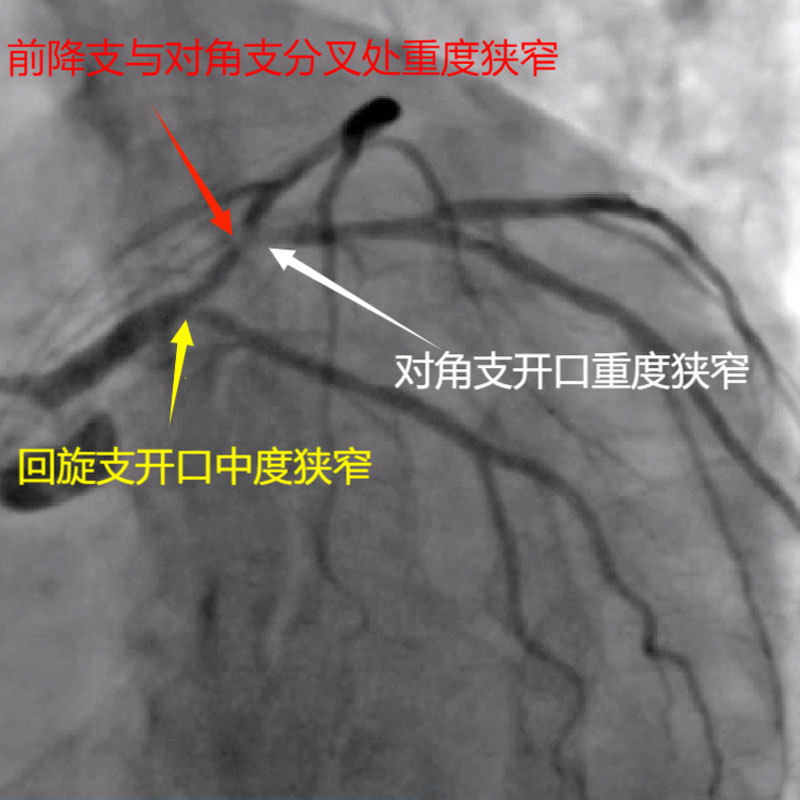

据了解,患者姓田,女性,58岁,本次因间断性胸闷、气促1周于来凤县人民医院就诊。既往有高血压病史多年,入院后评估患者心功能较差,择期冠脉造影提示前降支弥漫性病变伴重度狭窄,对角支粗大,开口严重狭窄,回旋支细小,中度狭窄,右冠轻度狭窄。因患者病情特殊性,心功能较差,多处分叉病变,边支不容丢失,属于高危风险手术人群,手术难度特别大,获得家属同意后,来凤县人民医院心血管内科介入团队决定为患者在IVUS指导下行Crush技术,经过2个半小时努力,成功为患者的分叉病变实行双支架植入。

来凤县人民医院副院长兼胸痛中心医疗总监张承中表示:经皮冠状动脉介入治疗(PCI)中分叉病变治疗颇为常见,约占30%,其处理是PCI的难点之一,也是近年来研究较多的热点;分叉病变的特殊在于,一支血管的PCI会影响分叉的另一支血管,造成或加重狭窄,甚至导致闭塞。该病人因心功能较差,而且多支分叉病变受累,边支不容有失,所以手术难度更大,团队经充分考虑后在IVUS指导下选择前降支及对角支分叉处采用Cursh技术,前降支及回旋支分叉处采用被动拘禁技术。